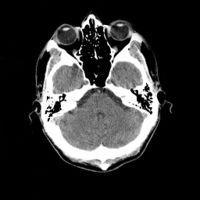

التصوير المَقْطَعي الحاسوبيX-ray computed tomography نظام تصوير بالأشعة السينية، يُسْتخدم لتصوير مختلف أجزاء الجسم مثل الرأس والقلب والبطن. ويستعين الأطباء بالتصوير المقطعي الحاسوبي على تشخيص الأمراض وعلاجها. وتسمى هذه التقنية أيضًا التصوير المقطعي المحوسب أو التصوير المقطعي المحوري المحوسب.

يمكن للأطباء أن ينظروا داخل جسم المريض عن طريق طلب إجراء مسح للعظام والأوعية الدموية والأدمغة والأنسجة الرخوة بفضل ماسح التصوير المقطعي الحاسوبي (CT). بعد إجراء أول فحص طبي بالأشعة المقطعية للمريض في عام 1971، استخدم أطباء الأشعة عمليات المسح لتشخيص الأورام والصدمات والتخطيط للعلاج الطبي والجراحي والإشعاعي في جميع أجزاء جسم الإنسان تقريباً.

يستخدم التصوير المقطعي المحوسب في تشخيص الأورام الخبيثة والحميدة في مناطق مختلفة في الجسم.